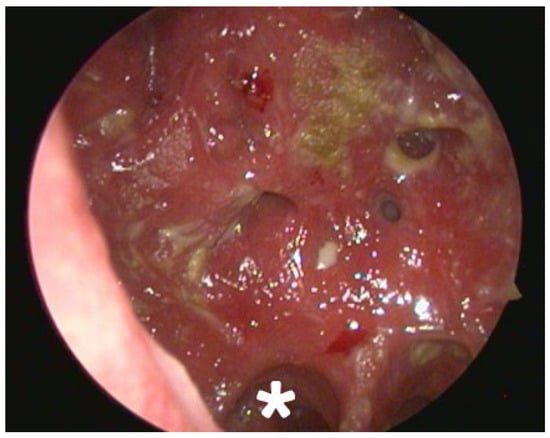

2.2. Clinical and Radiological Findings (2024)

- Mechanical Debridement: Daily endoscopic removal of all visible crusts and purulent debris was performed for the first two weeks of treatment.

| 2024 | Secondary atrophic rhinitis | Endoscopy, CT scan. Treatment initiation. 3-month follow-up. |